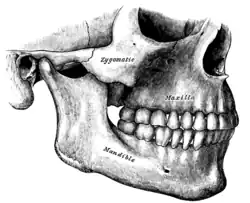

Maxilas em verde. Vista lateral.

Maxilas em verde. Vista lateral.- Modelo da maxila direita.

Maxila esquerda lateralmente.